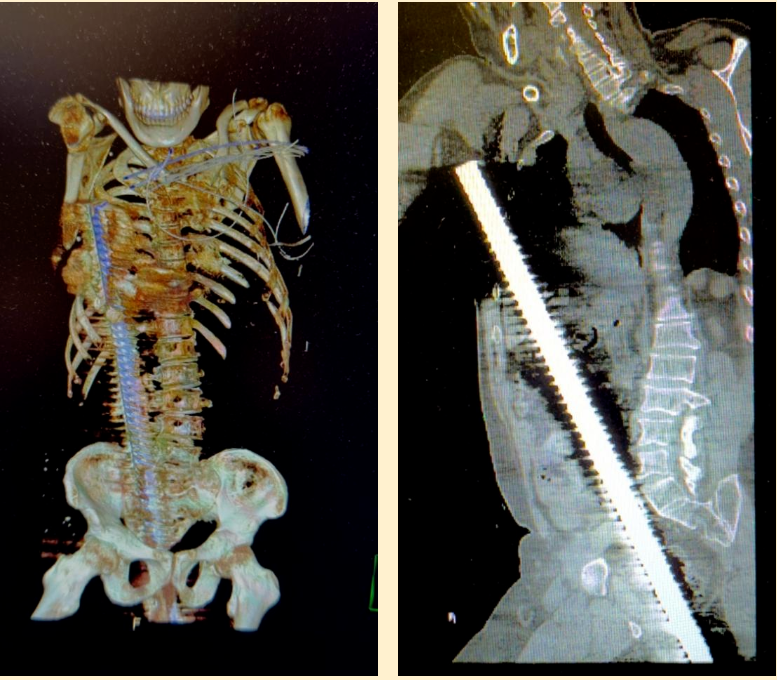

一位成年男性因意外不慎从高处坠落,一根直径 3 厘米的钢筋从会阴部贯穿盆腔、腹腔、胸腔直至右侧腋下,生命岌岌可危。

急诊医生接诊后,只见患者臀部附近露出一根长约 15 厘米,直径约 3 厘米的钢筋。当即启动创伤应急机制,迅速开通静脉通路、实施心电监护、快速补液稳定血压,伤者被快速送至急诊中心 CT 室进行全身扫描。影像显示,钢筋已贯穿盆腔、腹腔至胸腔,伤情凶险至极。急诊中心同步为患者实施深静脉穿刺置管,为输血、输液建立大流量通道。此时,医疗、护理、行政、院领导四大总值班接到汇报,迅速组织普外科、心胸外科、泌尿外科、创伤外科、ICU 等科室进行多学科 MDT 紧急会诊。

夜深人静的手术室灯火通明,监护仪的滴滴声、呼吸机的呼啦声显得格外清晰。「钢筋的位置靠近腹部大血管和肝门部,钢筋可能暂时压住出血点,如果贸然将钢筋拔除,可能导致灾难性大出血。」参加抢救的医生低声讨论着手术要点,大家个个神经紧绷、沉着应对。手术团队是嵇振岭教授、刘宗航副主任、强光辉副主任、以及于宽勇主治医生,台上台下,井然有序,配合默契。探查发现这根近 3 厘米粗的螺纹钢筋从会阴部刺入,经过盆腔穿透乙状结肠,紧贴腹部主动脉右侧挤压下腔静脉和髂血管,从后腹膜处穿过小肠系膜,横结肠系膜直达肝门右侧,在胆囊右侧进入肝脏,从肝脏膈面穿出,再穿透膈肌进入胸腔,直达右侧腋下。

患者伤情明确:会阴部盆腔穿透伤、乙状结肠穿透伤、小肠系膜穿透伤、横结肠系膜穿透伤、肝脏穿透伤、膈肌穿透伤、胸廓穿透伤等多重致命损伤。